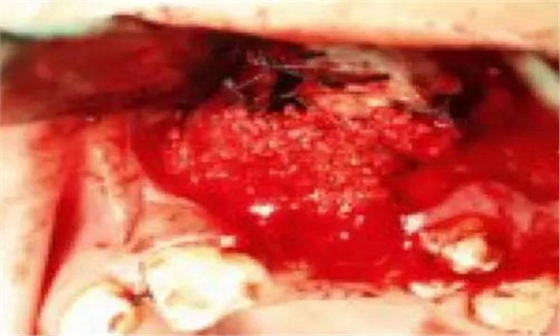

一名 23 區的9歲患者,在診所接受檢查時發現口內中存在大范圍含牙囊腫[圖1]。由于上頜竇下沿出現大范圍突出,迫切需要接受囊腫去除手術[圖2和3]。

3.jpg

術前全景片[圖1]

囊腫去除[圖2]

囊腫去除后的大量骨缺損[圖3]